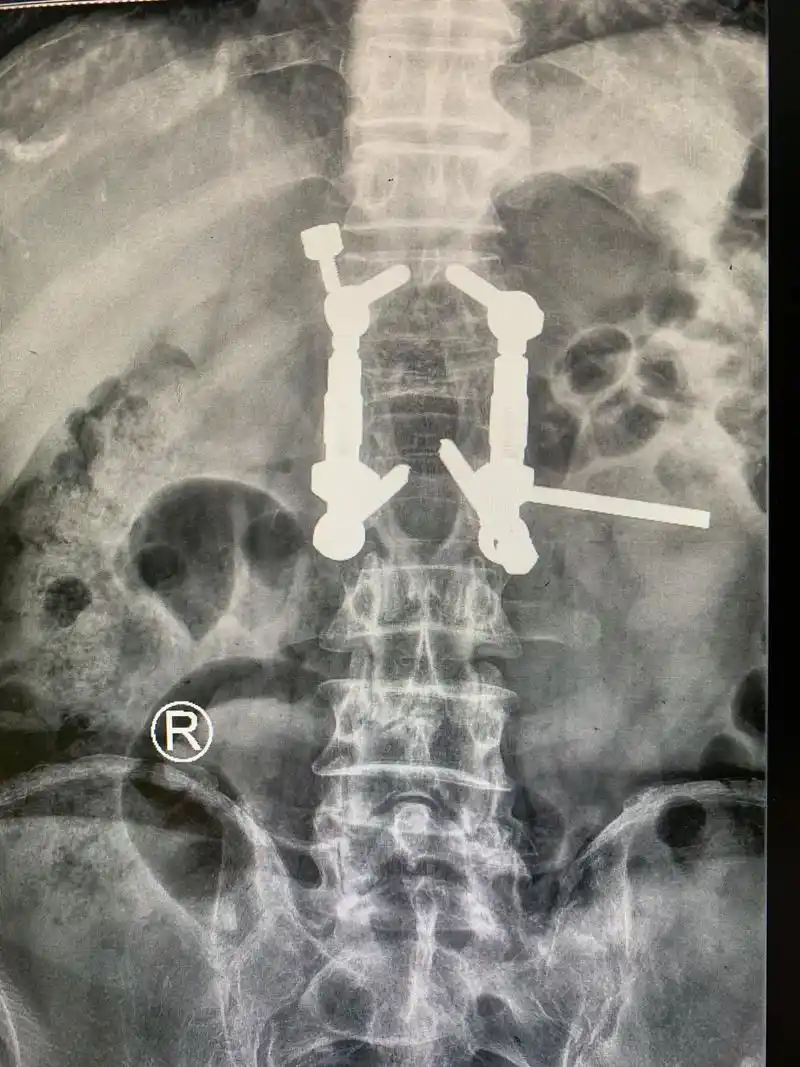

膨胀式椎弓根螺钉

一例椎弓根螺钉尾帽游离病例

canesp脊柱多轴椎弓根螺钉脊柱植入物

rf椎弓根螺钉系统和脊柱融合螺纹骨笼联合应用治疗脊柱滑脱_第1页

间融合器联合椎弓根螺钉系统治疗腰椎疾病临床疗效

五种提高骨质疏松患者椎弓根内固定强度的螺钉

腰椎双侧椎弓根螺钉固定三维有限元分析-上海赛一信息科技中心02